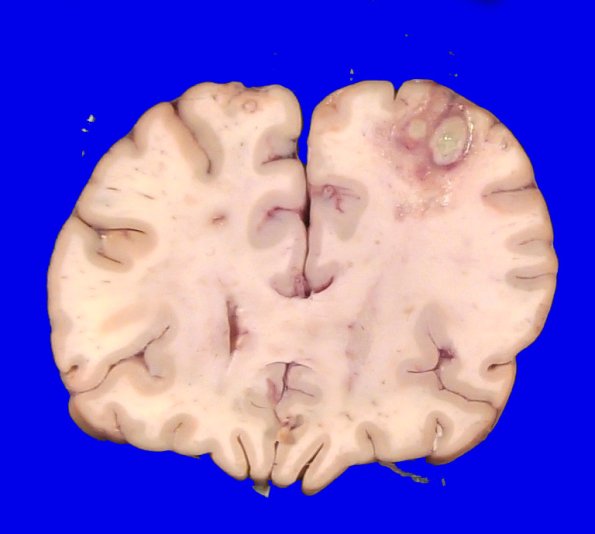

A coronal section of the frontal lobe showing multiple lesions and surrounding damage to the adjacent white matter.